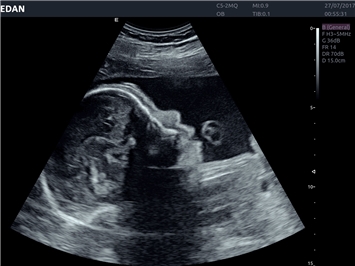

• 3D/4D-визуализация с автоматическим редактированием объема (eFace)

• Акушерства и гинекологии